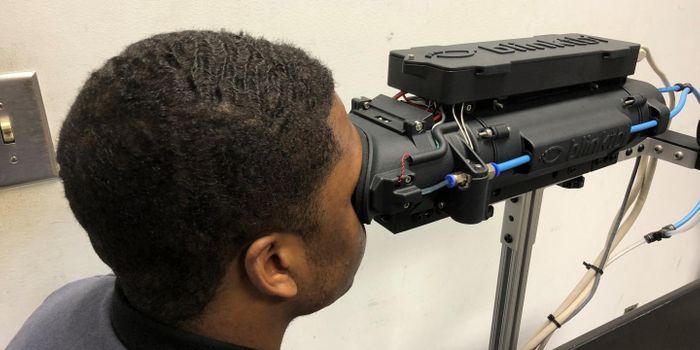

FEB 08, 2022Clinical & Molecular DXThe human skull is about a quarter of an inch of solid bone, perfectly suited to perform its role as the protecto ...